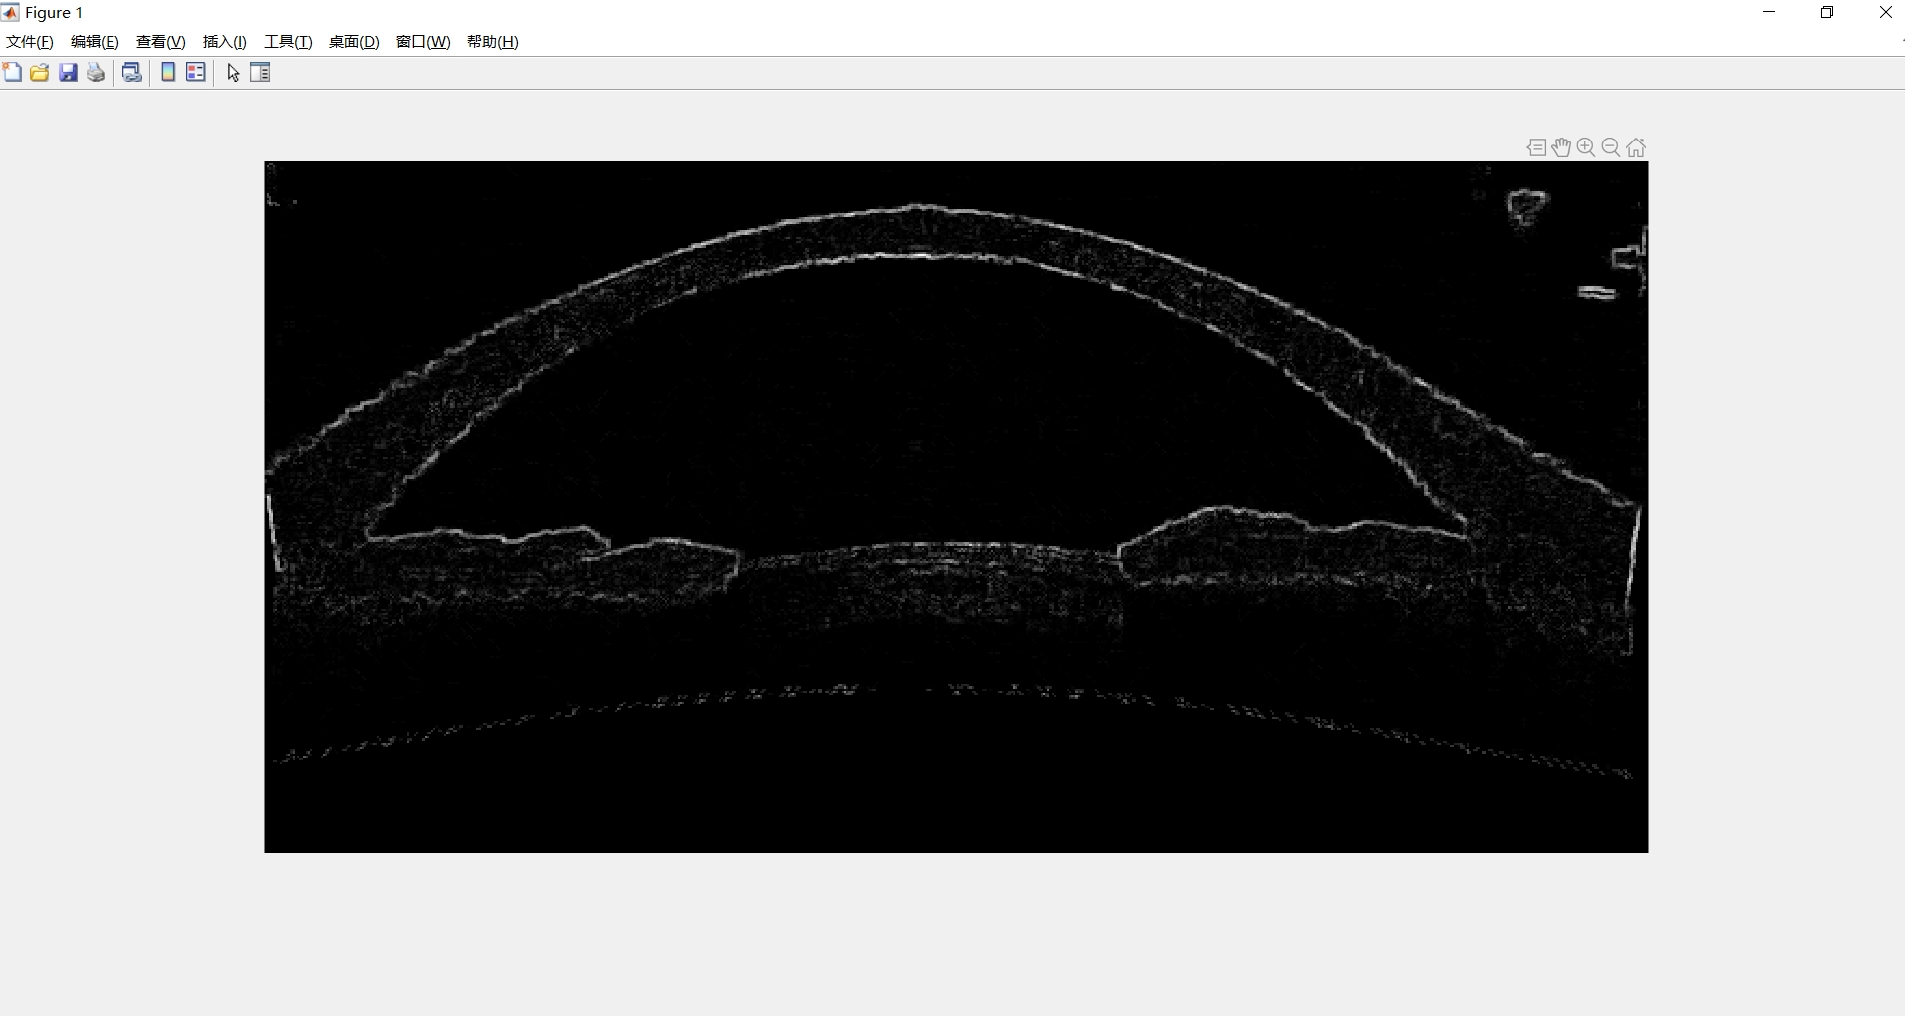

Matlab基于多尺度形态学提取眼前节组织

多尺度形态学分割的基本原理:数学形态学是处理和分析几何结构的一种基本技术,是一种基于集合理论技术,通常应用于图像处理中,是一种非常有用的图像分割工具。